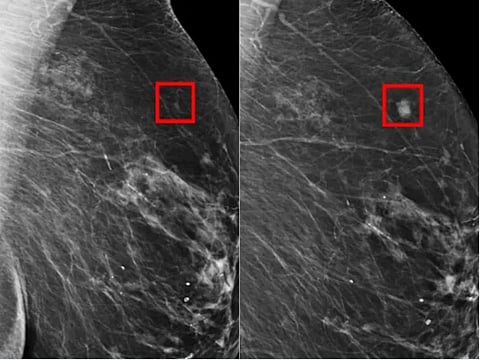

They were randomly sorted into two groups. In one, a single radiologist was assisted by an AI system to check the scans.

The AI model Transpara was trained on more than 200,000 previous examinations taken in 10 countries.